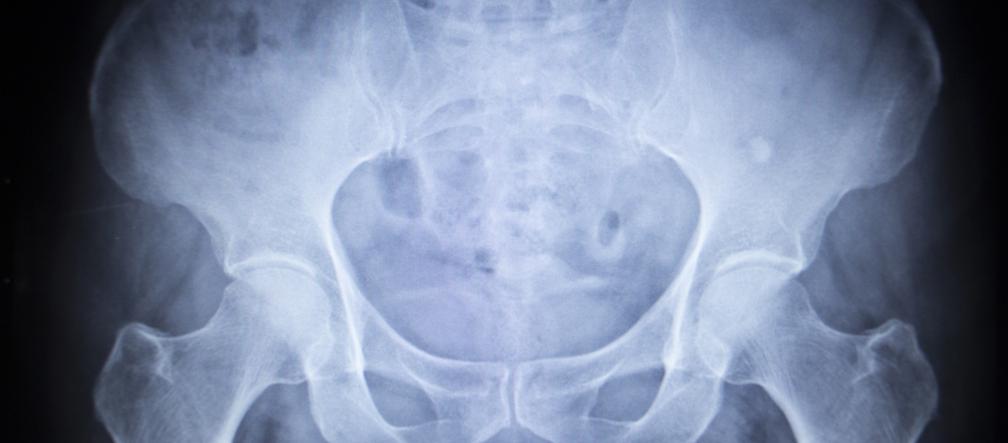

Autor: Thinkstockphotos.com/ Archiwum prywatne Cystografia - RTG pęcherza moczowego

Cystografia to badanie pęcherza moczowego, wykonywane z użyciem promieni rentgenowskich i kontrastu. RTG pęcherza moczowego pozwala ocenić wielkość i kształt pęcherza. Dostarcza także informacji na temat nieprawidłowości w funkcjonowaniu pęcherza moczowego.